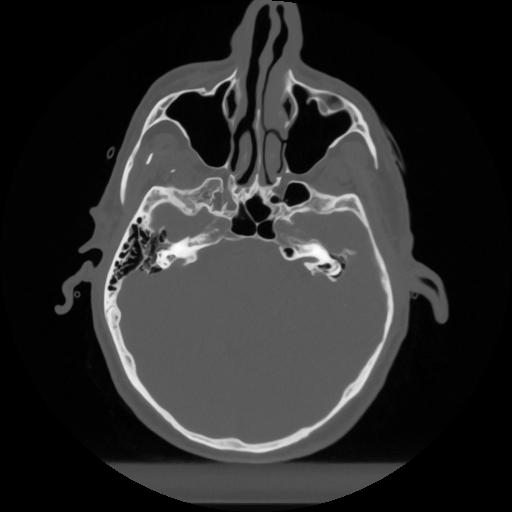

12 P.BLANDAS,,Vol,0.5,P.BLANDAS,,